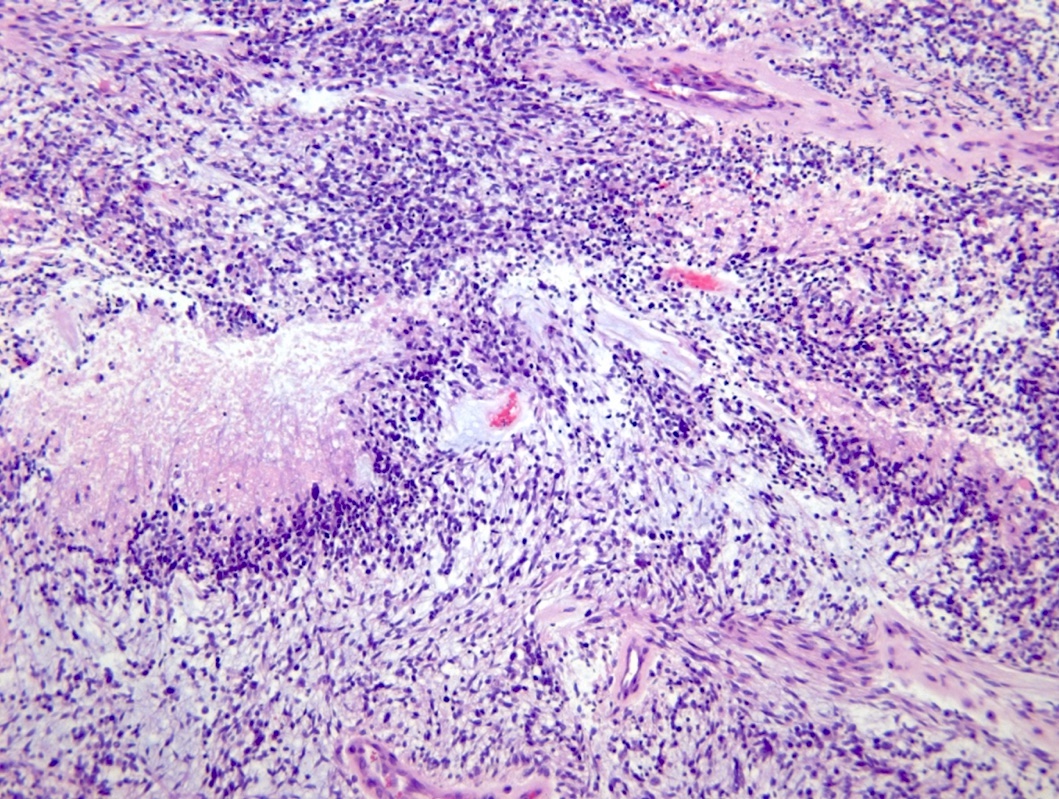

Microscopic (histologic) description

- Diffusely infiltrating tumor cells with oval to elongated astrocytic nuclei and varying appearance of tumor cytoplasm and fibrillar glial processes (Acta Neuropathol 2015;129:789)

- At the periphery, tumor cells may infiltrate in a diffuse single cell pattern, often with entrapped neurons and axons

- Cellular morphology is variable, even within a single tumor

- Commonly there is a mix of cells with elongated nuclei and fine fibrillar processes, cells with eccentric nuclei and glassy eosinophilic cytoplasm (gemistocytes), larger pleomorphic cells and small cells with scant cytoplasm

- May show oligodendroglioma-like areas

- Myxoid background and microcyst formation may be present

- Variable mitotic activity, cellularity and nuclear atypia depending on CNS WHO grade

- In small biopsy specimens, the presence of 1 mitosis may be sufficient for a CNS WHO grade 3 diagnosis, while the presence of a few mitotic figures in a large resection would not be sufficient for grade 3 designation (Acta Neuropathol 2020;139:603)

- Presence of necrosis or microvascular proliferation would be consistent with a CNS WHO grade 4 designation

Microscopic (histologic) images

Contributed by Eman Abdelzaher, M.D., Ph.D., John DeWitt, M.D., Ph.D. and Meaghan Morris, M.D., Ph.D.